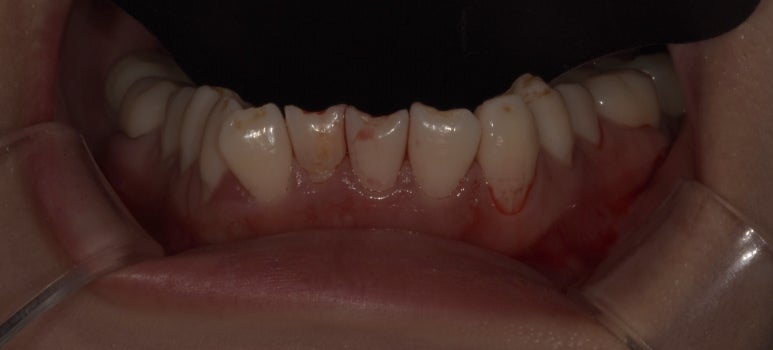

라미네이트, 올세라믹크라운 치료 전 하악 모습

2023-06-23

다른 치아는 모두 치아 앞 표면만 살짝 다듬어 라미네이트를 부착하는 방식으로 치료가 가능하지만,

#42 치아는 배열 개선을 위해 크라운 치료가 불가피해 해당 치아만 올세라믹크라운으로 치료 계획을 세웠습니다.

또한 해당 치아가 윗니와 닿지 않도록 교합을 정교하게 체크했고, 이갈이 장치도 함께 제작하기로 했습니다.

잇몸이 다소 부어있어서 잇몸치료를 병행하시기로 하고,